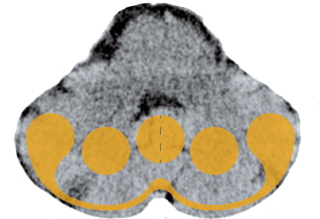

The trigeminus has three branches (see illustration p. 92): The upper, first branch, supplies the eye area, the second, essentially the nose and the third, the mouth and tongue. Usually the first branch reacts (migraines in the temple/eye area). As always, the content of the conflict reveals the function: